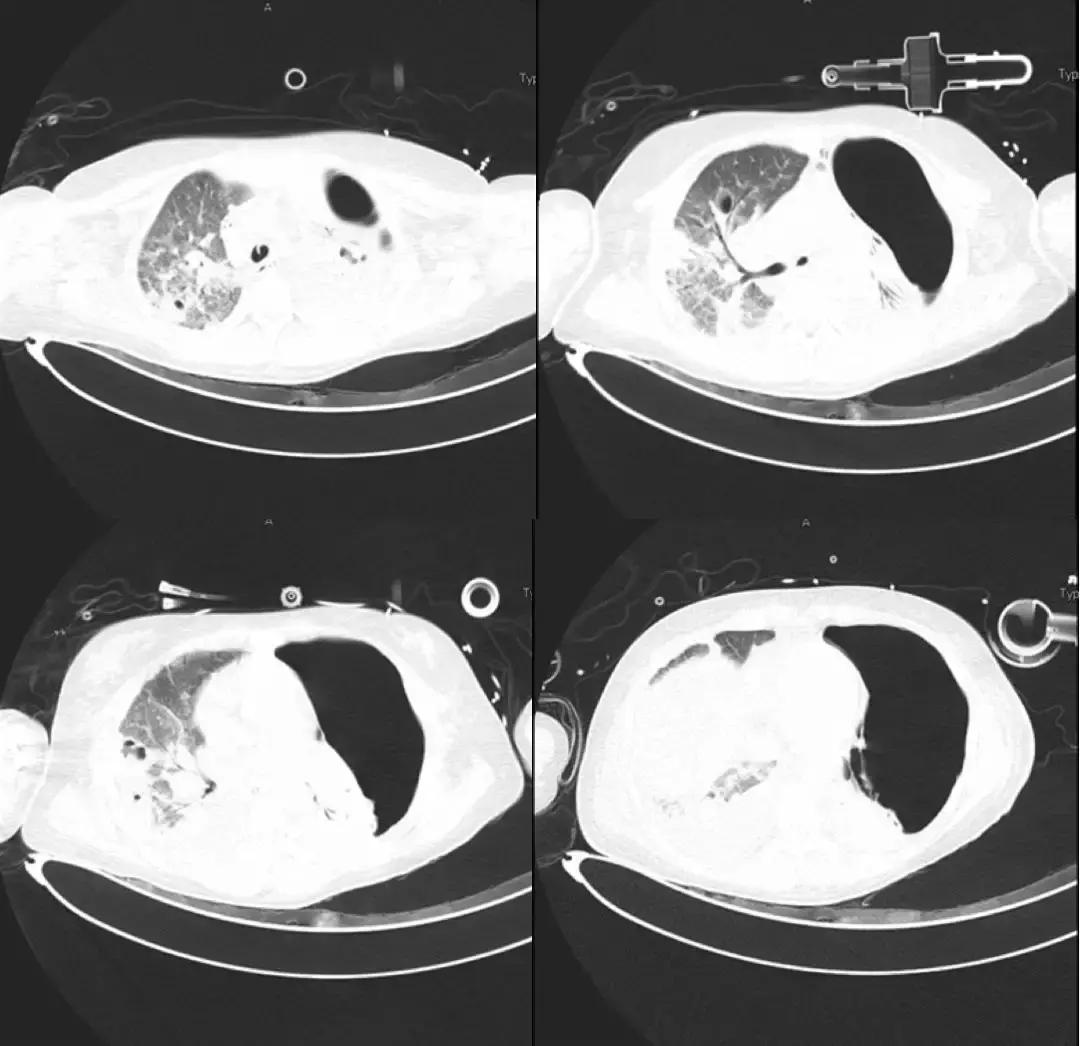

胸部CT(6月27日)提示双肺多发实变、斑片影、结节影。

*影像学显著进展

7月3日: